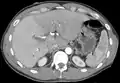

CT scan showing an adult liver in the axial plane.

Organogenesis, the development of the organs, takes place from the third to the eighth week during embryogenesis. The origins of the liver lie in both the ventral portion of the foregut endoderm (endoderm being one of the three embryonic germ layers) and the constituents of the adjacent septum transversum mesenchyme. In the human embryo, the hepatic diverticulum is the tube of endoderm that extends out from the foregut into the surrounding mesenchyme. The mesenchyme of septum transversum induces this endoderm to proliferate, to branch, and to form the glandular epithelium of the liver. A portion of the hepatic diverticulum (that region closest to the digestive tube) continues to function as the drainage duct of the liver, and a branch from this duct produces the gallbladder.[35] Besides signals from the septum transversum mesenchyme, fibroblast growth factor from the developing heart also contributes to hepatic competence, along with retinoic acid emanating from the lateral plate mesoderm. The hepatic endodermal cells undergo a morphological transition from columnar to pseudostratified resulting in thickening into the early liver bud. Their expansion forms a population of the bipotential hepatoblasts.[36] Hepatic stellate cells are derived from mesenchyme.[37]